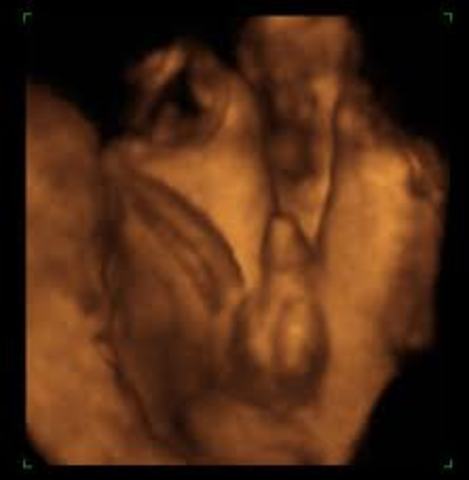

• Sex Determination

Sex Determination

The way doctors can tell what sex the baby is, is through an ultrasound. Determining the sex happens around the 15th week.